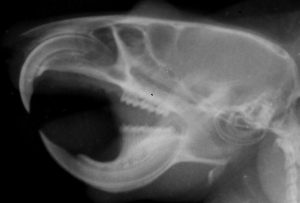

げっ歯類は、他の哺乳類グループと比較して、顎の咀嚼筋群と頭蓋骨の頬骨弓の解剖学的配置が非常に特徴的です〔Cox et al.2011,Cox et al.2012,Druzinsky 2010〕。の3つの咬筋が存在します。咀嚼筋群はいわゆる顎を閉める筋肉で咬筋(浅咬筋、深咬筋、頬骨下顎筋)、側頭筋、内側翼突筋、外側翼突筋からなります〔Cox et al.2012〕。咬筋は頭蓋骨の頬骨弓(人でいうところのほおぼね)と下顎骨の下側面を結ぶ、顎を前に引く筋肉になりますが、げっ歯類の咬筋は他の哺乳類と異なり、頭蓋骨では眼窩(Orbit: 眼球が入るソケット状の窪み)より前に広がり、下顎骨においては前方の臼歯の位置にまで達しており、 これらの特徴は、「かたいものをかじる獣」としての適応と深い関係があります。

モルモット型げっ歯類は、ネズミ型やリス型と比べて、拡大した咬筋の表層部分が下顎を前後に動かし、縮小した深層部分が顎を内転させて口を閉じるように構成されています〔Crossley 1991,Capelloet al.2005,Cox et al.2012〕。リス型げっ歯類では、深咬筋が吻側まで前方に拡大し、2つの部分(前部と後部)に分かれています。ネズミ型げっ歯類では、咬筋の両部分の起源が吻側まで前方に移動しており、協力して下顎を前後に動かすため、両方の摂食モード(切歯による齧り動作と臼歯による咀嚼動作)に等しく適応しています〔Cox et al.2012,Druzinsky 2010〕。リス型ならびにネズミ型げっ歯類の下顎は吻側尾側への広範囲な運動が可能であり、齧り食い時に吻側に亜脱臼することさえあります〔Crossley 1991,Nowak et al.1983〕。 顎が安静状態のとき、臼歯は咬合しており、下顎は短顎のような外観を呈します〔Crossley 1991,Nowak et al.1983〕。最終的に、切歯が齧り食いし、上下切歯の刃先が接近すると、臼歯の咬合が解除され、食物を咀嚼すると、下顎切歯が上顎切歯の後方に移動し、臼歯が再び咬合します。食物を粉砕する際には、下顎の上方および前方への運動が顕著となります〔Jekl 2009〕。咀嚼筋の解剖は様々ななげっ歯類の異なる食習慣や摂食戦略に反映されます〔Cox et al.2011,Yarto-Jaramillo 2011〕。リ型の深咬筋の吻側部の拡大は、切歯での噛む効率を高めます。逆に、モルモットの深咬筋が縮小しているのは、この種が主に頬歯で噛んで食べ、リスやネズミに比べて切歯で齧る時間が少ないことを示している可能性があります〔Druzinsky 2010〕。ネズミやリスは、主に植物を食べるモルモットよりも硬い食べ物 (ナッツや種子など) を多く消費します。ネズミ目はリス型とモルモット型の解剖学的特徴を融合し、齧りと咀嚼の両方で同等の効率を発揮するため、最も用途が広いです。これら2つの摂食様式は、上顎と下顎の長さの不一致により切歯と臼歯が同時に咬合できないため、互いに排他的です。したがって、これらの動作を行うには前歯列運動が必要です〔Becht 1953,Hiiemae et al.1968〕。